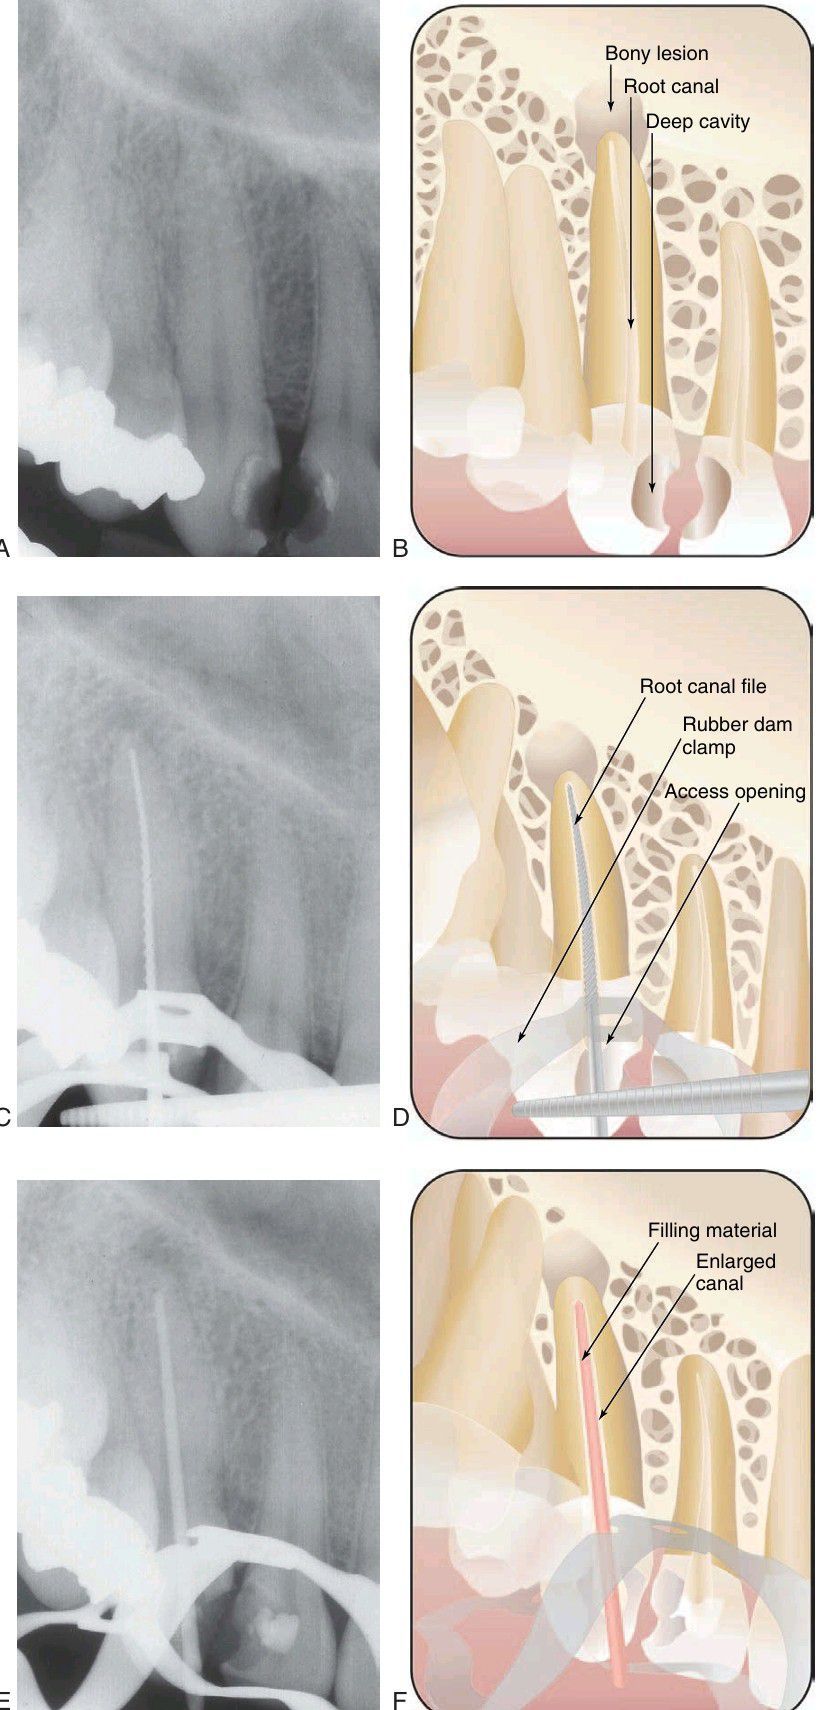

Series of radiographs and illustrations demonstrating root canal treatment and restoration of a maxillary canine. A-B, Maxillary canine with periradicular lesion of endodontic origin. C-D, Endodontic file corresponding to length of canal; isolation with rubber dam throughout procedure. E-F, Endodontic filling material placed after cleaning and shaping of canal. C